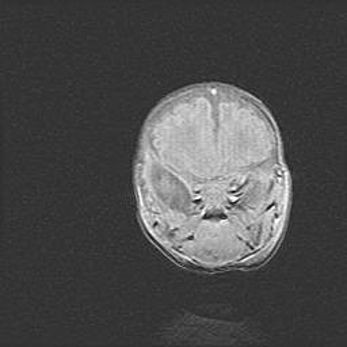

Мальформация Денди-Уокера. Киста задней черепной ямки.

Агенезия мозолистого тела.

Возраст: 2,5 месяца

Вес: 2420 г

Пол: женский

Окружность головы: 37 см

Срок гестации: 32 недели

Мальформация Денди—Уокера — редкий вид патологии ЦНС, представляющий собой врожденный порок развития каудального отдела ствола и червя мозжечка, ведущий к неполному раскрытию срединной (Мажанди) и латеральных (Лушка) апертур IV желудочка мозга. Для этогно синдрома характерна триада симптомов: гипотрофия червя мозжечка и/или полушарий мозжечка, кисты задней черепной ямки, гидроцефалия различной степени. В 70% случаев порок сочетается и с другими аномалиями головного мозга, в частности с агенезией мозолистого тела.